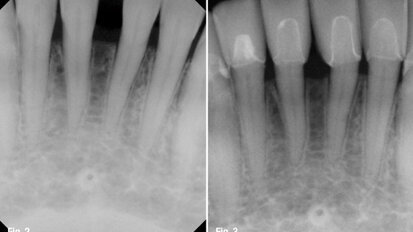

Visual information and imaging technology in endodontics

In addition to intra-oral and panoramic radiographs,various visual techniques are available for endodontic treatment today. Above all, information obtained ...